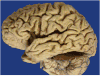

Context: Autopsy evaluation of the brain of a patient with frontotemporal dementia (FTD) can be daunting to the general pathologist. At some point in their training, most pathologists learn about Pick disease, and can recognize Pick bodies, the morphologic hallmark of Pick disease. Pick disease is a type of frontotemporal lobar degeneration (FTLD), the general category of pathologic process underlying most cases of FTD. The 2 major categories of pathologic FTLD are tauopathies (FTLD-tau) and ubiquitinopathies (FTLD-U). Pick disease is one of the FTLD-tau subtypes and is termed FTLD-tau (PiD).